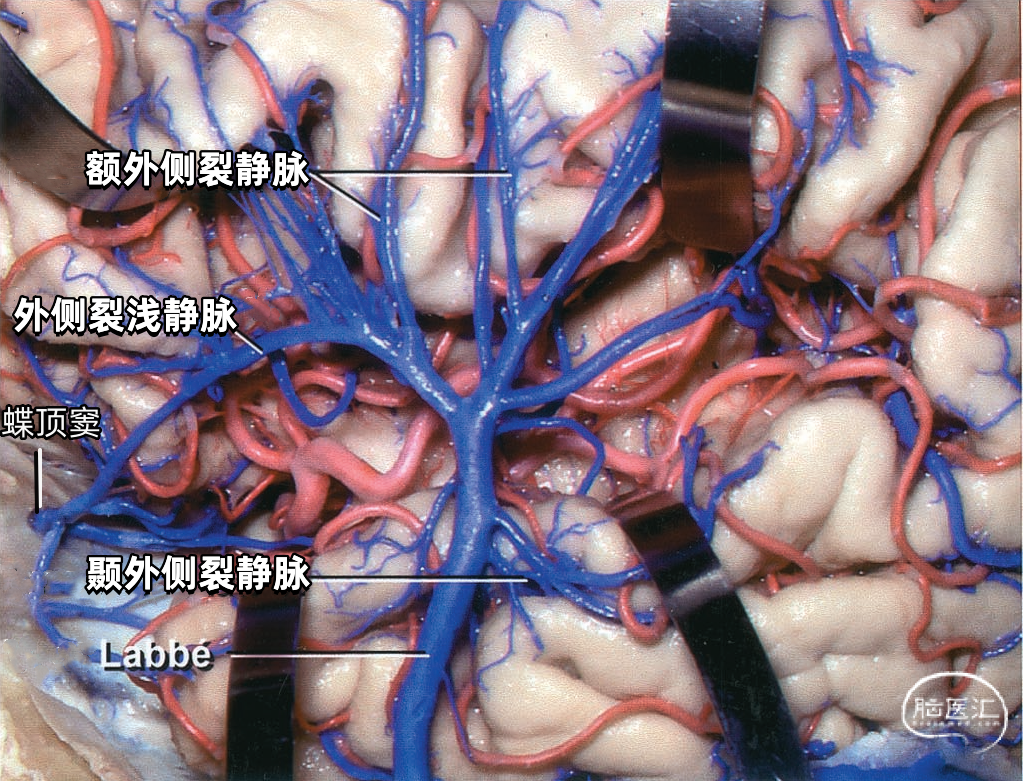

颞叶外侧面的皮层静脉可引流入横窦(上图),但在流入横窦之前,它们常向内沿颞叶底面进入小脑幕的短窦,此窦进入横窦末端之前在小脑幕内走行大约1cm。来自颞叶和枕叶底面的皮层静脉通常汇入外侧小脑幕窦。 Labbé静脉通常终于横窦(上图),但也可弧形围绕大脑半球下缘汇入外侧小脑幕窦。▼9.小脑幕窦

大脑外侧面最大的静脉是Trolard、Labbé、外侧裂浅静脉。 Trolard静脉是最粗大的吻合静脉,连接外侧裂静脉和上矢状窦。Labbé静脉则是连接外侧裂浅静脉和横窦的最粗大吻合静脉。外侧裂浅静脉沿外侧裂表面走行,而且主要沿蝶骨嵴汇入硬膜窦(蝶顶窦或海绵窦)。 虽然Trolard、Labbé静脉和外侧裂浅静脉大小可能相同,但更常见的是其中一支或两支血管比较粗大,而剩下的则细小甚至缺如。通常左右两侧血管的大小并不对称。

▼2.Labbé静脉

Labbé静脉也称下吻合静脉,是跨越颞叶外侧,连接外侧裂与横窦之间的最大吻合静脉。它通常起自外侧裂中部,行向后下,进入横窦前部。 Labbé静脉经过颞叶表面的位置有可能非常靠后甚至位于颞叶的最后界,或非常靠前达颞叶前1/3的外侧面。在此研究的20例半球中,12例Labbé静脉位于颞中静脉水平,6例位于颞后静脉水平,2例位于颞前静脉水平。有时会有两条Labbé静脉,其中后支通常会粗大一些。

下图示右颞叶和外侧裂。外侧裂浅静脉的前部细小,而汇入Labbé的后部粗大。一支颞中静脉沿颞上沟形成一桥静脉,跨过半球下缘汇入小脑幕窦。外侧裂浅静脉还通过两条Trolard静脉与上矢状窦吻合:一条经过额叶,另一条经过顶叶。颞外侧裂静脉引流颞上回,汇入外侧裂浅静脉和颞中静脉。

下图示横窦和小脑幕窦的分支。抬起颞叶的后部,暴露进入横窦的Labbé静脉、颞后静脉和枕后静脉,从颞叶底面进入小脑幕窦的颞底静脉。

▼3.外侧裂浅静脉

外侧裂浅静脉通常起自外侧裂后端,沿外侧裂唇行向前下。它可能以两支起始,但通常在沿蝶骨嵴进入静脉窦之前融合为一支。 外侧裂浅静脉接受额外侧裂静脉、顶外侧裂静脉和颞外侧裂静脉的回流,并经常与Trolard静脉和Labbé静脉相吻合。它穿经覆盖外侧裂前端的蛛网膜,在蝶骨嵴内侧部下方加入蝶顶窦,或直接进入海绵窦。它也有可能离开外侧裂,围绕颞极,进入中颅窝底的硬膜窦,引流入岩上窦,或通过蝶骨的小孔出颅与翼静脉丛相交通。 如果外侧裂浅静脉细小或缺如,则相邻的静脉将代替引流其区域。起自外侧裂上唇的静脉,向上引流加入进入上矢状窦的静脉;起自外侧裂下唇的静脉,直接向后下,汇入颞叶下方的硬膜窦。如果外侧裂浅静脉的中部缺如,则静脉前部加入蝶骨嵴的硬膜窦,而后部则加入Trolard和Labbé吻合静脉。